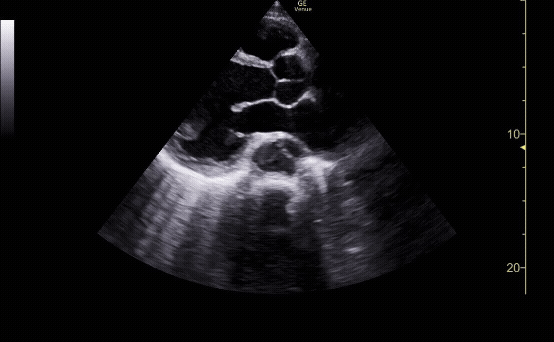

Parasternal long view showing the right ventricle, left ventricle, left atrium mitral valve, aortic root, and descending aorta.

c/o Kyle Ackerman, MD